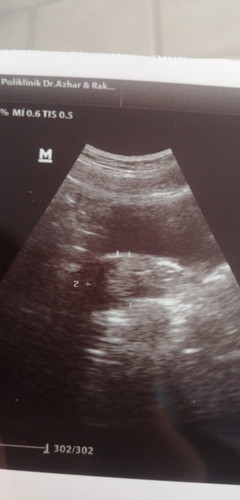

Hai mommy, saya nak tanya yang pernah jadi mcm saya.. scan mcm ni maksud ada ke? sebab doktor tak bagi kepastian lagi, then cek upt naik 2 line tapi satu line masih kaboq. so kalau tengok pada scan ni biasa ada isi ka? sbb tak nmpak kantung dan upt masih kaboq.. kalau ikut period saya dah dari bulan 2 tk datang. ada turun darah 2 hari ja tu pun sikit and tk sakit or sengugut apa pada bulan 27/3.. ada sesiapa penah jadi?